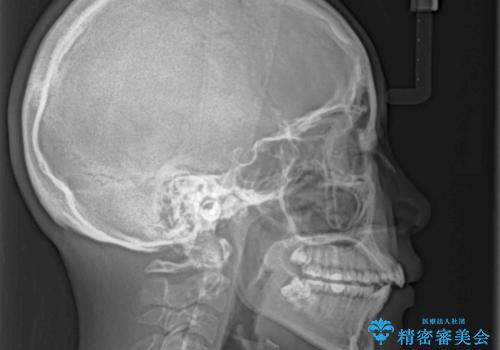

- デコボコと飛び出した前歯を治したいとのことで来院された患者様です。

ゴムかけを活用して上顎歯列全体を後方移動し、IPR(歯と歯の間を削る)によってデコボコが解消するように設計し、インビザラインにより治療を行うこととしました。

後方移動に際し、上下顎の親知らずは4本とも抜歯することとしました。